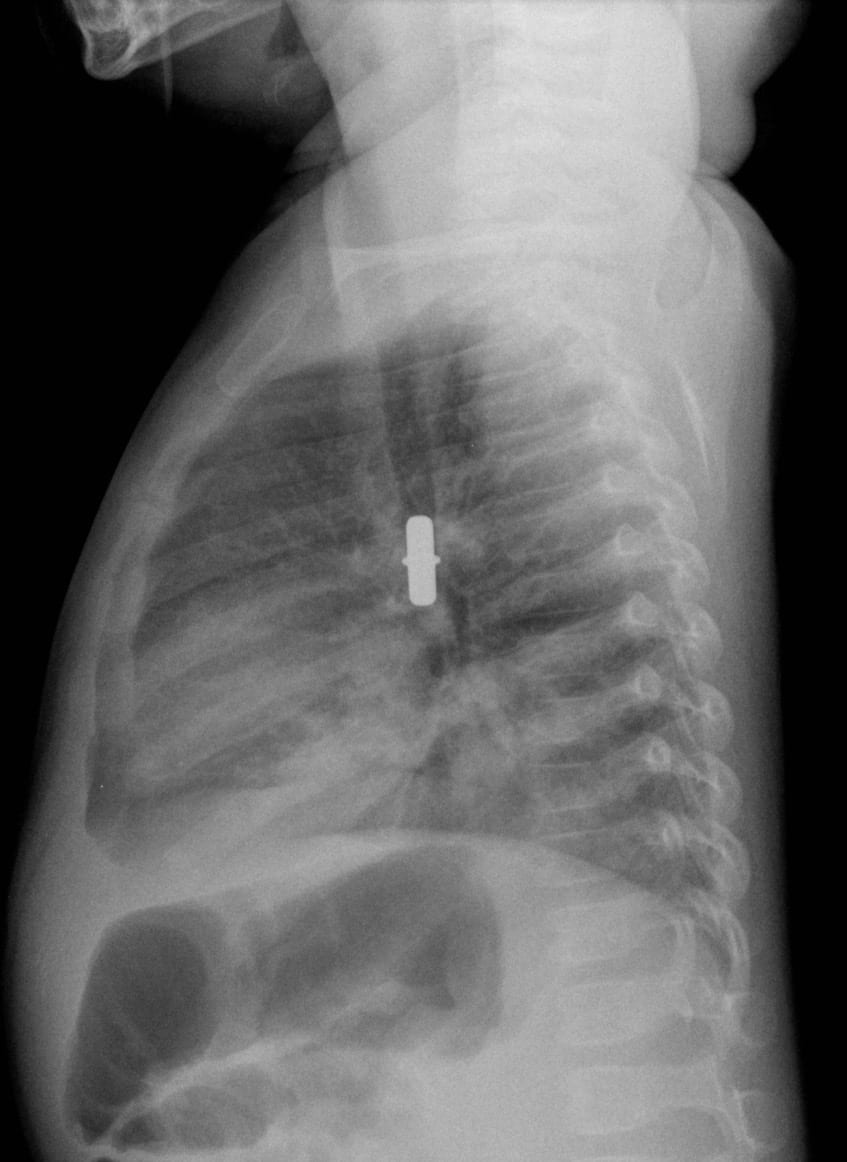

From radiopaedia.org

Inhaled foreign body Image What Happened To The Size Of Your Chest When You Inhaled When you inhale (breathe in), air enters. when the diaphragm contracts, it flattens and increases the chest cavity. This increases the space in. diseases & conditions / hyperinflated lungs. the severity of the symptoms depends on the size, nature and location of the inhaled object. Now exhale and observe the opposite events occurring. Hyperinflated lungs are when. What Happened To The Size Of Your Chest When You Inhaled.

From litfl.com

Inhalational Emergency • LITFL • Clinical Cases Paediatric What Happened To The Size Of Your Chest When You Inhaled the elasticity of the lungs and chest wall, which are actively stretched during inhalation, causes them to return to their resting shape and to expel air out of the. as you inhale, you may feel the air pass down your throat and notice your chest expand. when the diaphragm contracts, it flattens and increases the chest cavity.. What Happened To The Size Of Your Chest When You Inhaled.

From www.wikiradiography.net

Chest Radiography for Inhaled Foreign Body wikiRadiography What Happened To The Size Of Your Chest When You Inhaled Now exhale and observe the opposite events occurring. When you inhale (breathe in), air enters. This increases the space in. when you breathe in, or inhale, your diaphragm contracts and moves downward. Hyperinflated lungs are when your lungs expand beyond their. when the diaphragm contracts, it flattens and increases the chest cavity. the elasticity of the lungs. What Happened To The Size Of Your Chest When You Inhaled.

From www.pinterest.com

Expiratory chest x ray examination in the diagnosis of inhaled foreign What Happened To The Size Of Your Chest When You Inhaled This increases the space in. as you inhale, you may feel the air pass down your throat and notice your chest expand. the severity of the symptoms depends on the size, nature and location of the inhaled object. since the parietal pleura is attached to the thoracic wall, the natural elasticity of the chest wall opposes the. What Happened To The Size Of Your Chest When You Inhaled.